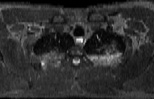

Visible Human male: Sectio transversalis 1328

CT

NMR

Pd T1 T2